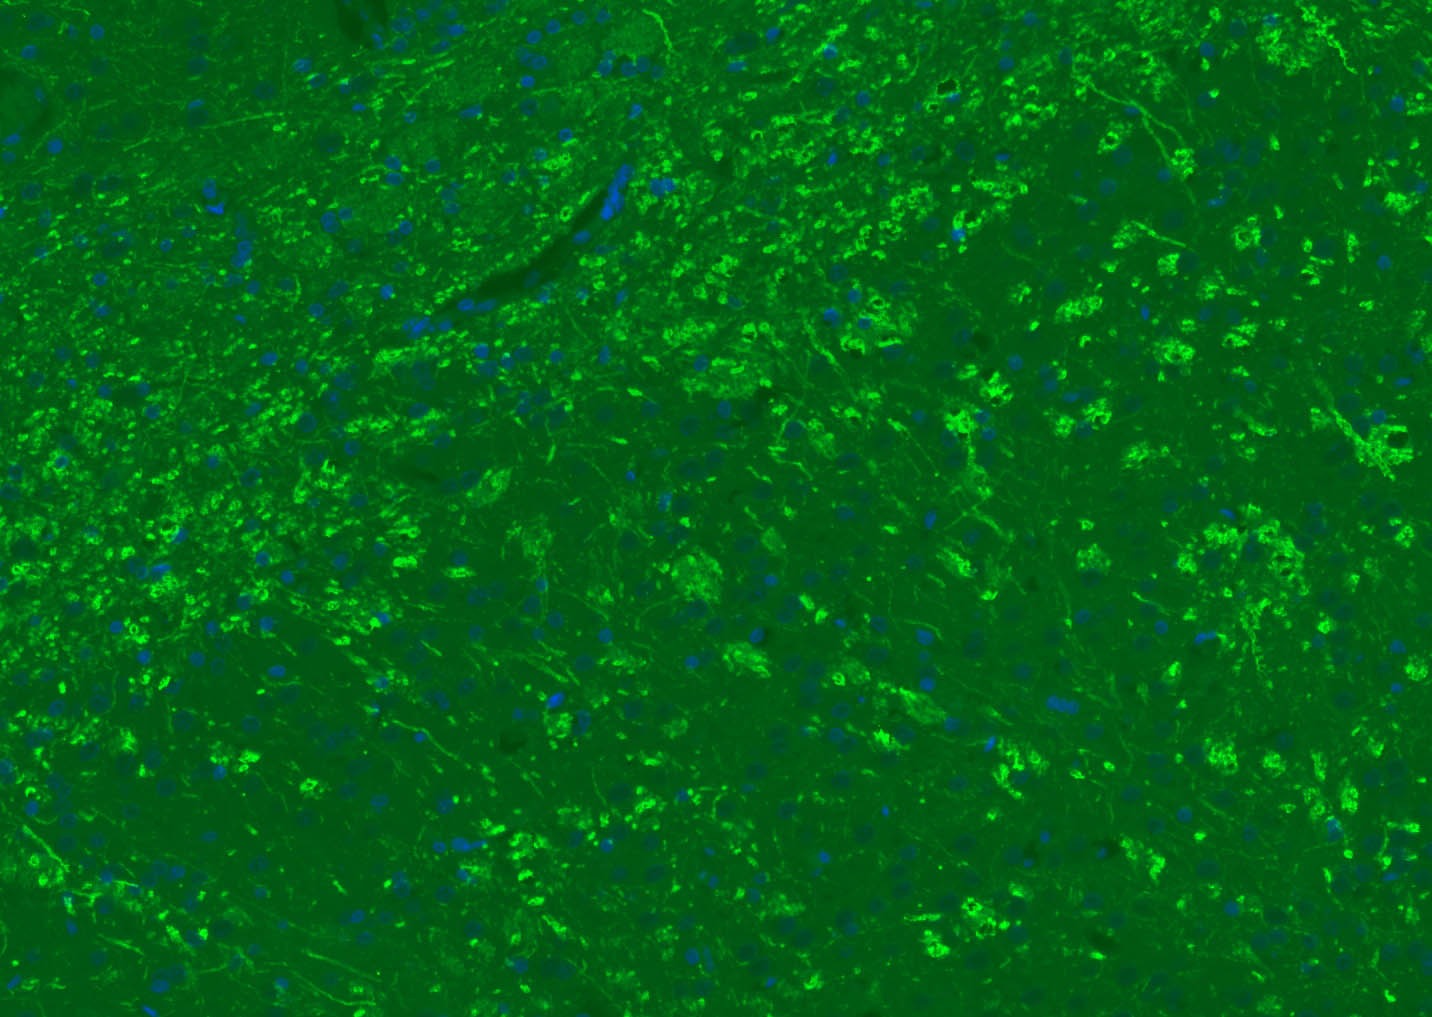

2. Paraformaldehyde-fixed, paraffin embedded (rat brain); Antigen retrieval by boiling in sodium citrate buffer (pH6.0) for 15 min; Blocking buffer (normal goat serum) at 37°C for 30 min; Antibody incubation with (MBP) Polyclonal Antibody, Unconjugated (TMAB-01110) at 1:200 overnight at 4°C, followed by a conjugated Goat Anti-Rabbit IgG antibody for 90 minutes, and DAPI for nucleus staining.

3. Paraformaldehyde-fixed, paraffin embedded (human brain); Antigen retrieval by boiling in sodium citrate buffer (pH6.0) for 15 min; Blocking buffer (normal goat serum) at 37°C for 30 min; Antibody incubation with (MBP) Polyclonal Antibody, Unconjugated (TMAB-01110) at 1:200 overnight at 4°C, followed by a conjugated Goat Anti-Rabbit IgG antibody for 90 minutes, and DAPI for nucleus staining.